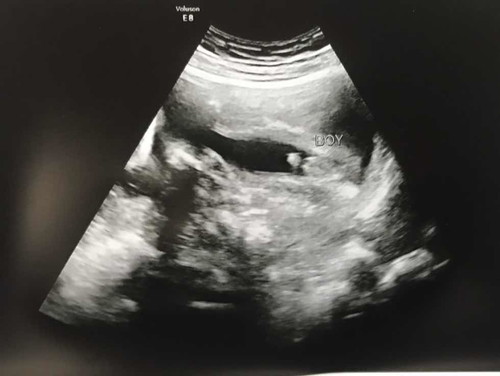

??คุณหมอบอกว่าหนูเป็นเด็กชาย 99% เลยครับ ?แม่ลุ้นมาก หนีบมาจนครบ 6 เดือนเลยลูกเอ้ย ?สมใจอิแม่จิงๆ ลูกชายยย